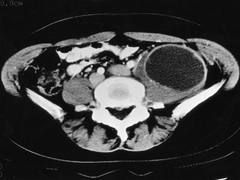

난소 낭종(Ovarian cysts)

관련질환

다낭성 난소 증후군

,

난소의 양성 종양

난소암

난소, 난관 이상

관련용어

양성물혹

양성낭기형종

여성호르몬대체요법